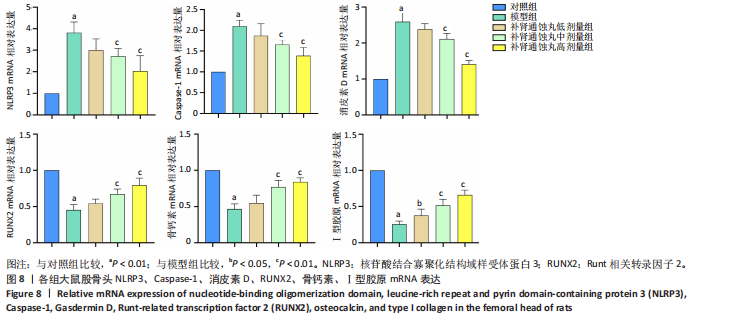

素D-N蛋白表达均显著上调(P < 0.01),成骨因子Runt相关转录因子2、骨钙素、Ⅰ型胶原蛋白表达均显著下调(P < 0.05);补肾通蚀丸各剂量组NLRP3、cleaved-Caspase-1、Caspase-1、消皮素D、消皮素D-N蛋白表达以一定剂量依赖方式呈现不同程度的下调,Runt相关转录因子2、骨钙素、Ⅰ型胶原蛋白表达则以一定剂量依赖方式呈现不同程度的上调;与模型组比较,补肾通蚀丸中、高剂量组NLRP3、cleaved-Caspase-1、Caspase-1、消皮素D、消皮素D-N蛋白表达均显著下调(P < 0.05),补肾通蚀丸高剂量组Runt相关转录因子2、骨钙素、Ⅰ型胶原表达均显著上调(P < 0.01),补肾通蚀丸中剂量组Runt相关转录因子2蛋白表达显著上调,而骨钙素、Ⅰ型胶原表达无明显差异(P > 0.05),补肾通蚀丸低剂量组Runt相关转录因子2、骨钙素、Ⅰ型胶原表达均无明显差异(P > 0.05),见图7A,B。与对照组比较,模型组cleaved-Caspase-1/Caspase-1比值和消皮素D-N/消皮素D比值均显著上升(P < 0.01);与模型组比较,补肾通蚀丸中、高剂量组cleaved-Caspase-1/Caspase-1比值和消皮素D-N/消皮素D比值均显著下降(P < 0.01),而补肾通蚀丸低剂量组cleaved-Caspase-1/Caspase-1比值与对照组比较无明显差异(P > 0.05),见图7C。 2.7 RT-qPCR检测结果 RT-qPCR结果显示,与对照组比较,模型组大鼠股骨头组织中NLRP3、Caspase-1、消皮素D mRNA表达显著上调,Runt相关转录因子2、骨钙素、Ⅰ型胶原mRNA表达显著下调(P < 0.01);与模型组比较,补肾通蚀丸中、高剂量组NLRP3、Caspase-1、消皮素D mRNA表达均显著下调,Runt相关转录因子2、骨钙素、Ⅰ型胶原mRNA表达均显著上调(P < 0.01),而补肾通蚀丸低剂量组NLRP3、Caspase-1、Runt相关转录因子2、骨钙素mRNA表达均无明显差异(P > 0.05),见图8。"